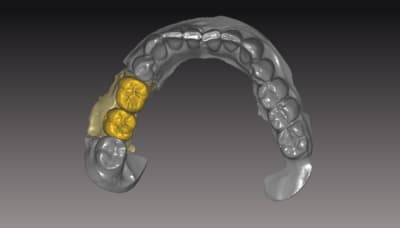

donc voici comme promis piliers ZR sur base Titan

passivité total de l'armature , les piliers sont tous réglés , parallélisés lors de la modélisation de l'ensemble . l'usinage des piliers et de l'armature ce fait séparement pour encore qualité d'ajustage..

Dans le ce cas present Strauman BL 3.3 rc

collage des base titan avec du multilink automix

ce cas est en cour de réalisation , essayage de l'ensemble

déja validé ... je n ai pas de eu de photos , aucun blanchiment de gencive , merci l'ajustage des profils d'émergence dans le soft qui est vraiment bien fait ..

*

a suivre..

je m'éclate vraiment avec les possibilitées qu'offrent le system d'usinage ...

Pour l'instant 100% de client satisfait pourvu que ca dure....